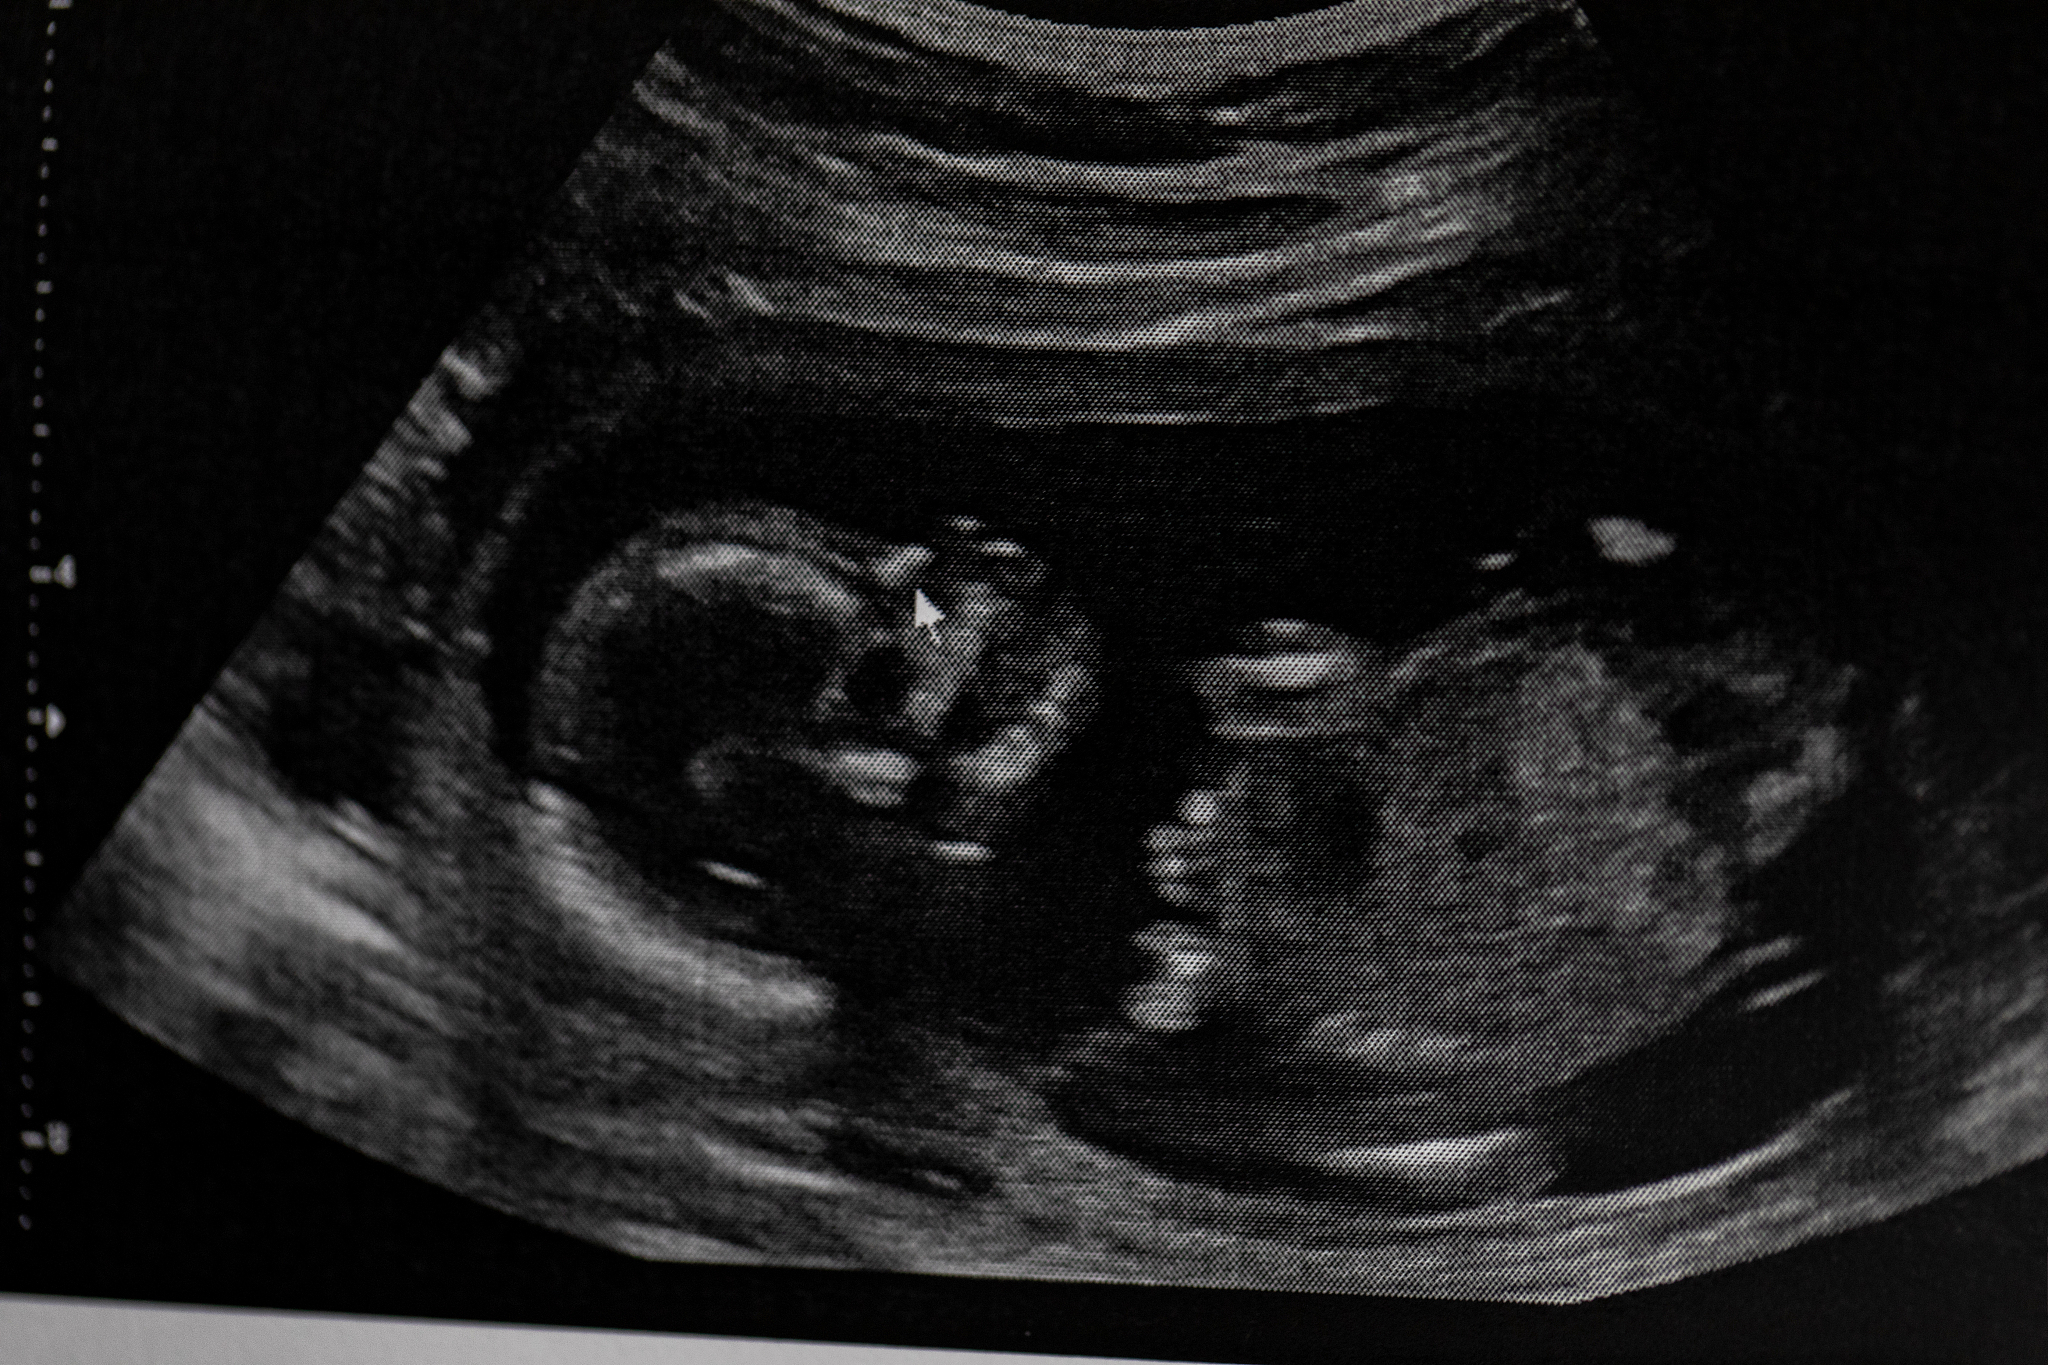

为进一步明确诊断,经过患者知情同意进行了超声造影检查,显示稍低回声的斑块内存在大量新生血管(图1),伴随着斑块局部纤维帽的不连续,宽度约为1.4mm,深度约为4.0mm,并充满造影剂(图2)。